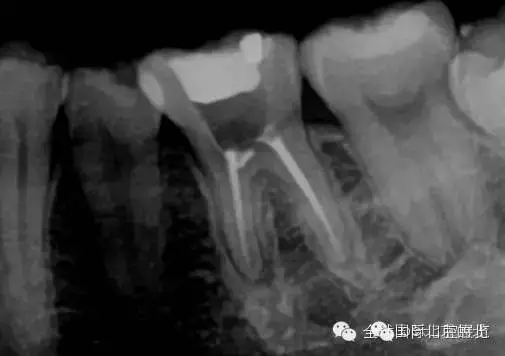

終于完成根充

MM,ML其實(shí)融合為一個(gè)根管口的,截面就是三根管的形態(tài),然后做了一個(gè)簡(jiǎn)單清晰的三維重建,形態(tài)還是挺不錯(cuò)的 。

一個(gè)月后復(fù)查,如果無(wú)明顯反應(yīng)就進(jìn)行及時(shí)的冠修復(fù),做好冠方封閉